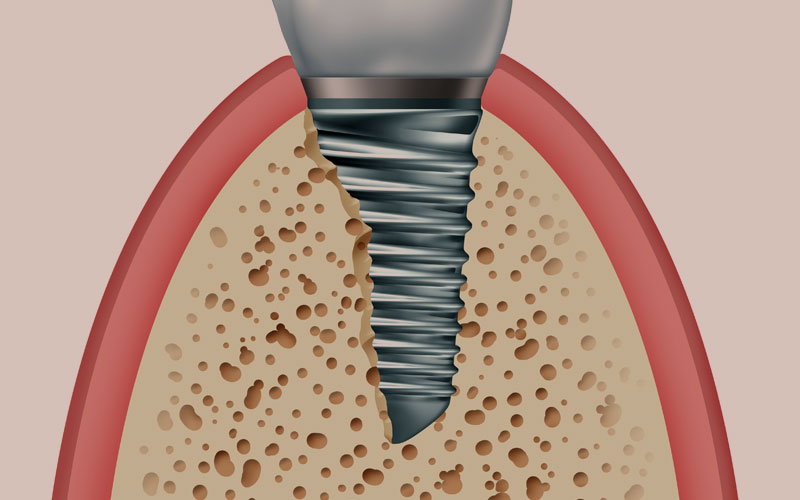

インプラントそのものはチタンで出来ています。歯の根と同じように約10mm程度の長さをしているチタン製の人工物が、歯の根の代わりにあごの骨に埋め込まれます。

インプラント体の素材であるチタンには、時間の経過とともに骨と一体化して固まってしまう性質があり、この作用を利用して、人工の歯の根をしっかりと固定させています。インプラントはネジの様な形状で溝が刻まれており、スクリューさせてあごの骨にしっかりと埋め込めるようになっています。またインプラントのメーカーごとに、より良く骨と結合させるために工夫が凝らされた表面形状で作製されており、これがメーカーごとの大きな性能の違いとなっています。